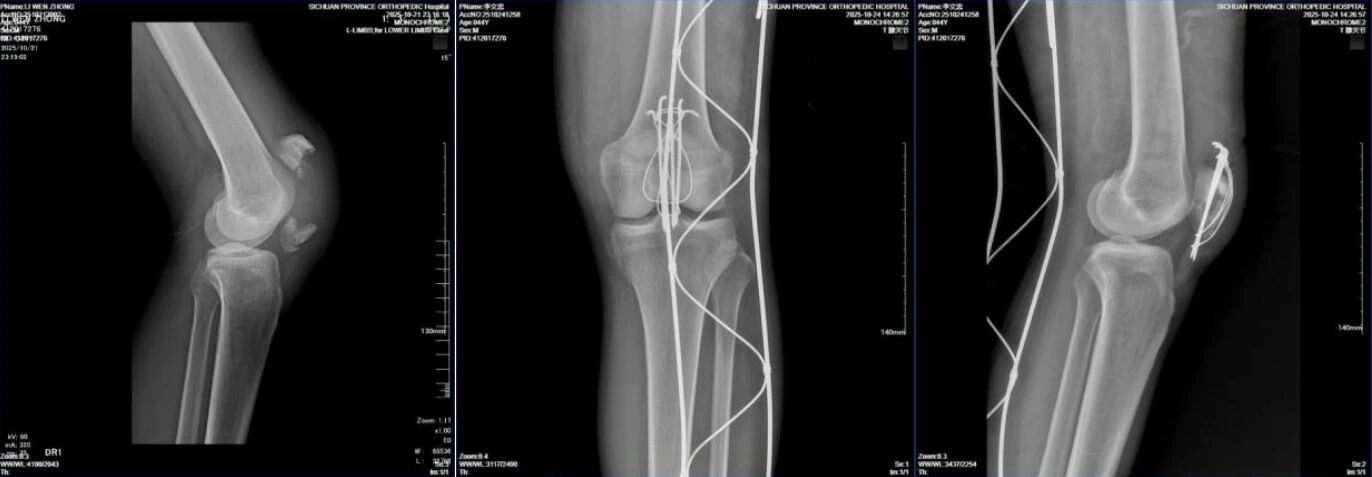

44岁男性患者,左髌骨粉碎性骨折。

自左向右:术前DR侧位片,术后复查DR正、侧位片